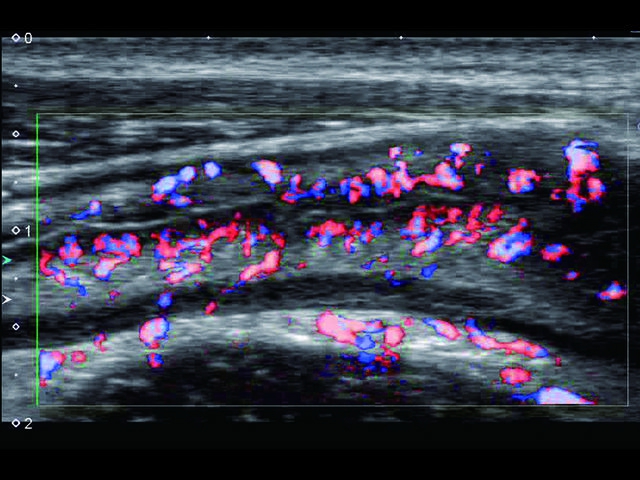

• SMI. Опция, упрощающая визуализацию микроциркуляторного русла. С ее помощью обследуются сосуды с низкой интенсивностью кровотока, изучаются наиболее тонкие структуры. SMI упрощает диагностику новообразований, минимизирует вероятность ошибки.

Обновленная версия легендарного УЗ-сканера. Стационарный аппарат экспертного класса Aplio 500 Toshiba NEW, визуализирует анатомические структуры в высоком разрешении. Модель позволяет выявить микрокальцификаты, новообразования, нарушения в работе сердца, сосудов и мышц. Присутствует функция виртуальной эндоскопии, 4D-сканирования, эластометрии тканей, УЗИ с контрастированием. За повышение качества изображения отвечают технологии ApliPure и Superb Microvascular Imaging. Первая задействует возможности пространственного и частотного кодирования, формирует цельный визуальный ряд с сохранением клинических маркеров. Вторая улучшает отображение микрососудистого русла, используя доплеровский эффект. Модель оснащена 21-дюймовым монитором, имеет 4 активных порта. Возможно подключение педиатрических, интраоперационных, лапароскопических и чреспищеводных датчиков.